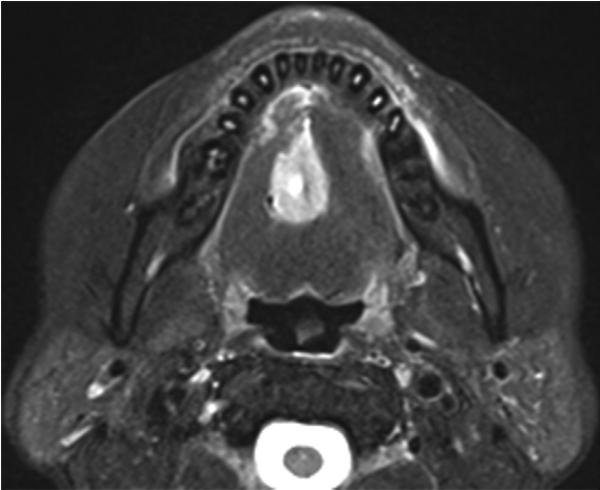

患者60岁,上腹不适2个月,自行服用法莫替丁。患者称喉咙痛和舌痛越来越重。于2015年10月就诊,患者第一次就诊时舌面粘膜完好(图1),但是触诊时发现舌背有一个硬的粘膜下肿块,未发现明显的颈部淋巴结病变。

图1 患者第一次就诊时舌面粘膜完好

磁共振成像(MRI)显示舌内肌内1.5×2.3×2.0cm的肿瘤。肿瘤在T1加权像上呈低信号,在T2加权像上呈非均匀高信号(图2)。PET/CT发现舌肿瘤;胰腺体肿瘤从脾静脉侵犯到前面肾旁间隙;多发性肝肿瘤;肺肿瘤;盆腔内的腹膜肿块被认为是播散性的(图3A和B)。CT增强扫描显示胰体肿瘤广泛侵犯脾窦静脉至肾旁前间隙。附着在胰腺肿瘤上的胃浆膜层被破坏,肿瘤侵入胃壁(图4)。因为胃的大部分解剖形态保持不变(图4),所以被认为是胰腺癌侵犯胃,而不是胃癌侵犯胰腺。

图2 MRI对T2加权图像进行轴位观察。MRI在T2加权像上表现为不均匀的高强度异质性病变。肿瘤贴附于右侧舌下腺。